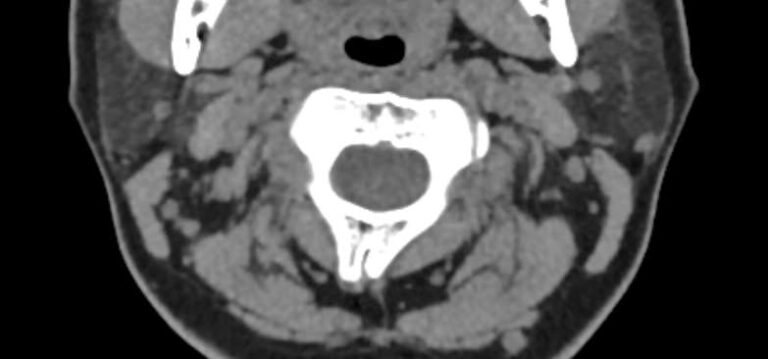

Одним из наиболее информативных методов диагностики заболеваний краниовертебрального перехода является мультиспиральная компьютерная томография с возможностью объемной реконструкции изображений. В основе методики лежит использование рентгеновского излучения. КТ позволяет детально визуализировать костные структуры позвонков, выявить нестабильность суставов, смещение зубовидного отростка и оценить степень сдавления спинного мозга.

Кроме нативной КТ в ряде случаев показано проведение исследования с внутривенным болюсным контрастированием. Методика используется для лучшей визуализации патологических очагов. Для этого пациенту внутривенно вводится йодсодержащий контрастный препарат. Контрастное вещество накапливается в патологических участках и обеспечивает их яркую визуализацию на фоне неизмененных тканей. С помощью контрастирования можно визуализировать кровеносные сосуды, выявить первичные опухоли и метастазы в костных структурах, степень их прорастания в окружающие ткани, дифференцировать новообразования, например, отличить доброкачественную опухоль от злокачественной.

При проведении мультиспиральной КТ можно диагностировать различные заболевания, в том числе, аномалии развития краниовертебральной области (как врожденного, так и приобретенного происхождения):

- смещение шейных позвонков в результате травм;

- дегенеративно-дистрофические заболевания данной области;

- воспалительные и аутоиммунные заболевания с поражением краниовертебрального перехода;

- опухолевые образования.